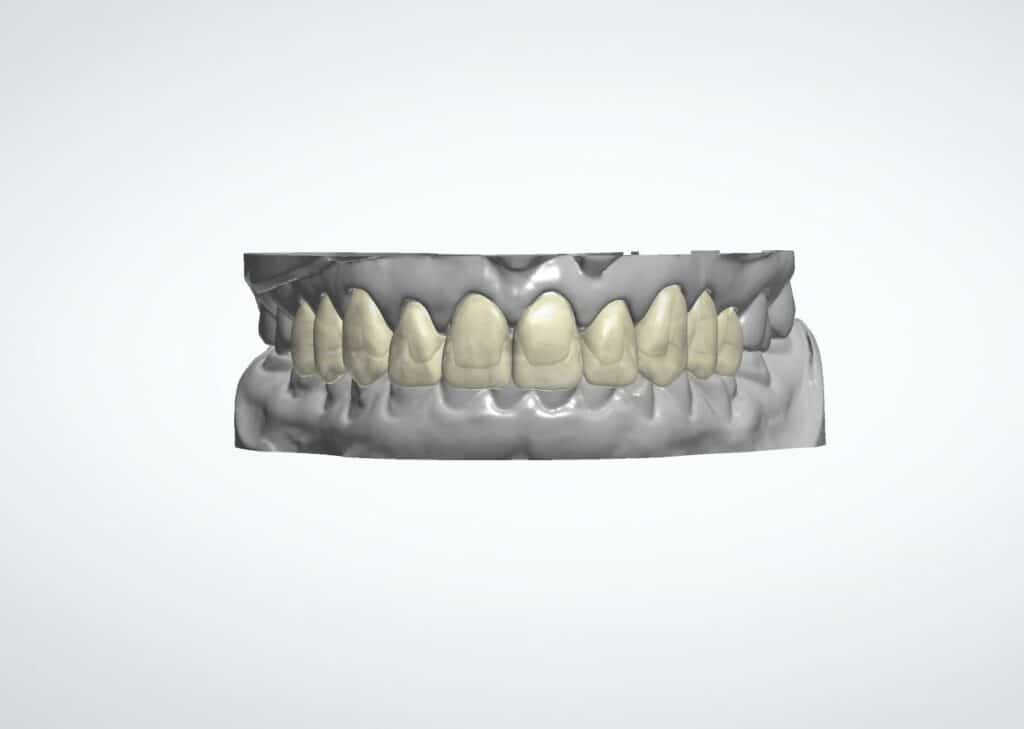

Der am Monitor visualisierte Vorschlag der verlängerten Zahnkronen mit provisorischen Restaurationen wurde mit der Patientin in der Praxis in Anwesenheit des Autors besprochen (Abb. 4 und 5).

Mit dem realen Bild der Patientin und einem biometrischen Smile Design, das ihren Gesichtsproportionen entsprach und die ursprüngliche Zahnkronenlänge be-rücksichtigte, war die Patientin schnell überzeugt.